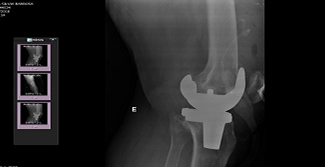

files/img.ptg.2.1.02.23039.jpg

Rastreabilidade do material no pós-cirúrgico.